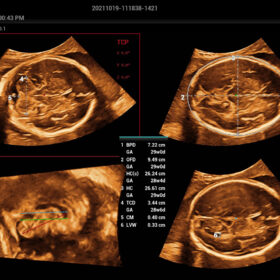

- Smart OB – Accurate auto measurements of most frequently examined parameters BPD/HC/FL/AC/OFD with a single click